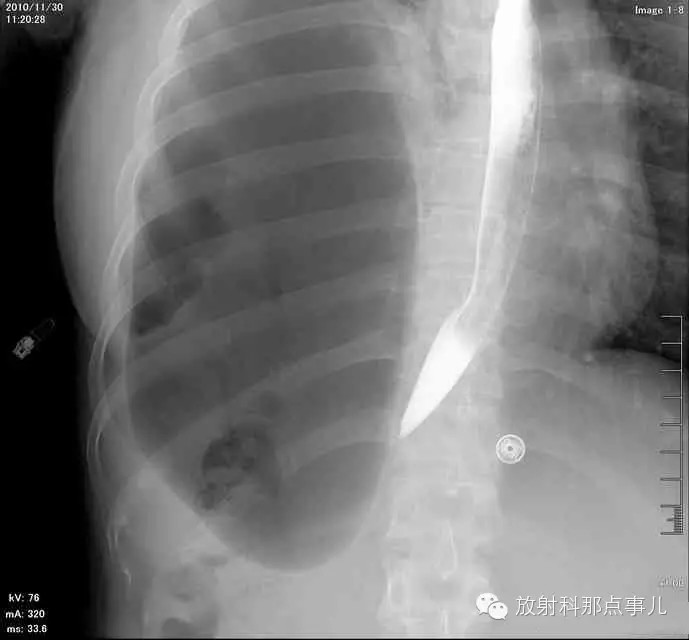

【病例学习】膈疝一例X线诊断

24岁,女性,腹痛渐加重并呕吐。

患者系顺产后18天产妇,产后感觉腹部疼痛不适,自认为正常反应,近两日因胸闷、腹部疼痛加剧伴呕吐来院就诊。

门诊腹部透视发现左侧胸腔巨大气液平面,为排除膈疝口服钡剂,但造影剂未见进入胃内。嘱住院,外科给予胃肠减压、补液等处理常规处理(未引流出明显气、液体)。5个半小时后再次检查,见少量造影剂进入消化道;为进一步了解情况,予泛影葡胺分别经胃管推注及口服,但均未进入胃内。当天进行外科急诊手术。

大部分胃、脾及横结肠均经过胸肋三角疝入左侧胸腔内,并见疝环形成。